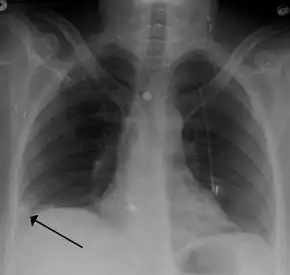

Pulmonary embolism (white arrow) that have been long-standing and has caused a lung infarction (black arrow) seen as a reverse halo sign.

- Chest X-rays are often done on people with shortness of breath to help rule-out other causes, such as congestive heart failure and rib fracture. Chest X-rays in PE are rarely normal,[59] but usually lack signs that suggest the diagnosis of PE (for example, Westermark sign, Hampton's hump).